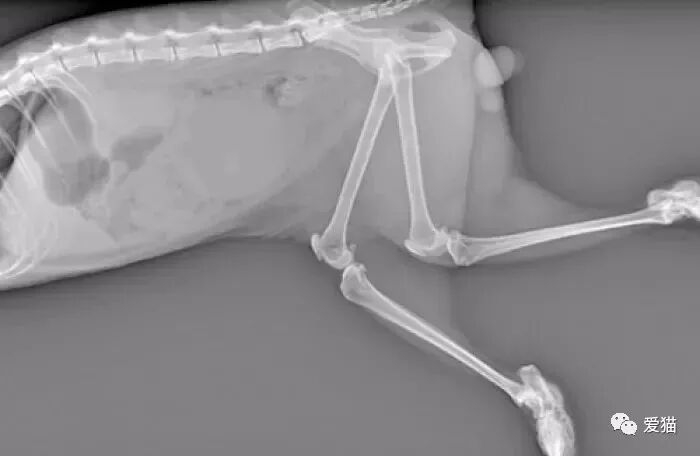

发病的折耳猫,拍的x光照片,骨骼已变形。

唯一办法就是只能用药物舒缓病情,帮助猫咪减轻楚痛及减慢恶化速度。当病情恶化起来,骨骼病变的情况慢慢蔓延至脊椎,导致折耳猫瘫痪,引致极大的痛楚。